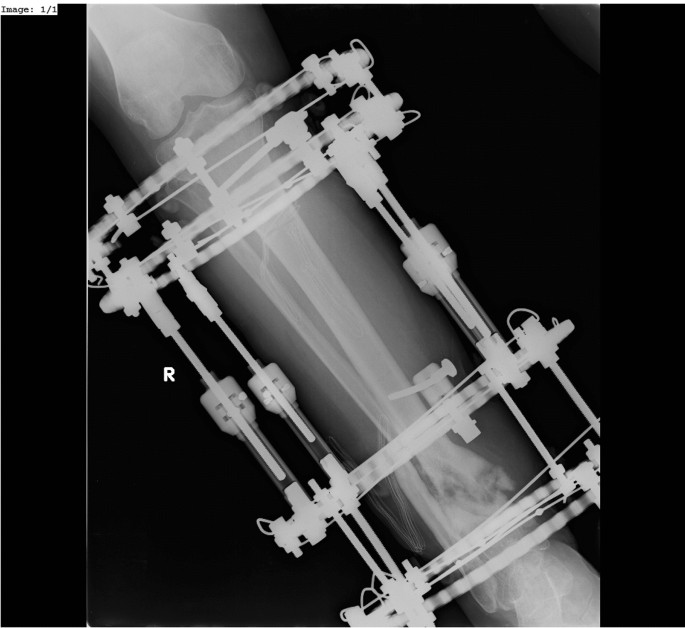

The purpose of our study was to assess the results of treatment with the Ilizarov method in patients with aseptic nonunions of the tibia, depending on the employed treatment strategies and surgical techniques (Figs. 2, 3).

All surgical procedures were conducted by three experienced orthopedic surgeons. In the case of nonunions of the proximal and middle thirds of the tibia, the Ilizarov external fixator consisted of four rings fixed to the tibia and fibula with Kirschner wires. In the case of nonunions involving the distal tibial metaphysis or epiphysis, the Ilizarov fixator consisted of three rings (fixed to the tibia and fibula with Kirschner wires) and a foot frame stabilized with three olive wires.

The treatment of nonunions of the tibia with the Ilizarov method was conducted with various strategies and surgical techniques, selected based on the condition of bone and soft tissues, type of nonunions, shape of bone fragments, limb length discrepancy, limb deformity, and operator’s preference. The selected tactics of surgical management can be divided into two techniques and two strategies. The evaluated patients underwent either closed (technique 1) or open (technique 2, with open, small resection of bone fragments, with adaptation of the edges of the nonunion and stabilization). The operators used one of two treatment strategies: either neutral fixation without compression (strategy 1) or continued compression (adjusted by 0.25 mm every 3 days) until bone union within the location of the nonunion was achieved, as confirmed by radiographic and clinical evidence (strategy 2). All patients underwent fibular osteotomy. We used to cut fibula routinely, to ensure that during stabilization or compression of the nonunion, the fibula does not block or stiffen tibia.